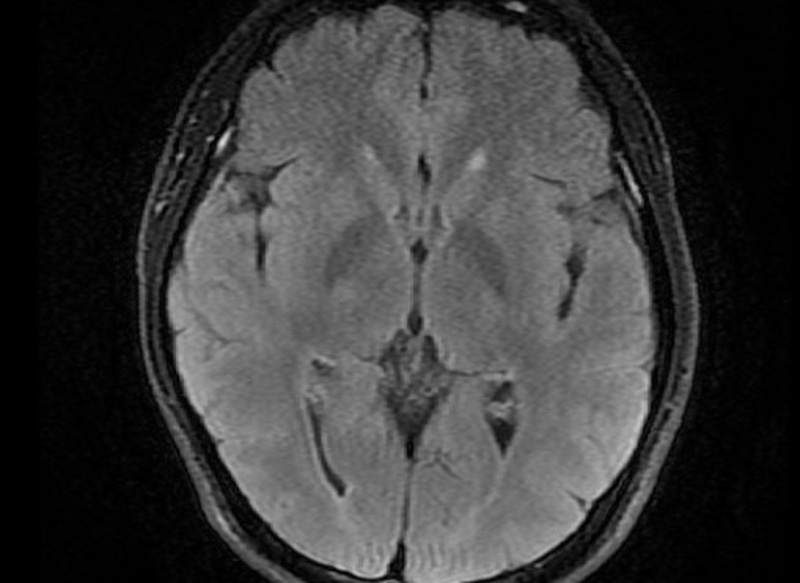

Ngay khi tiếp nhận thăm khám, nhận thấy tình trạng bệnh nhân liệt nửa người phải, thất ngôn, kết quả chụp CT não không thấy tổn thương do xuất huyết não. Các bác sĩ chẩn đoán: Bệnh nhân bị nhồi máu não cấp giờ đầu, khởi động quy trình điều trị bệnh nhân đột quỵ não cấp, xử trí dùng thuốc tiêu sợi huyết đường tĩnh mạch cho bệnh nhân.

Sau tiêm thuốc 30 phút, cơ lực của bệnh nhân cải thiện, tỉnh táo trở lại, nửa người phải dần cử động được. Sau điều trị phục hồi chức năng 3 ngày, bệnh nhân đã phục hồi, nói chuyện, đi lại được.